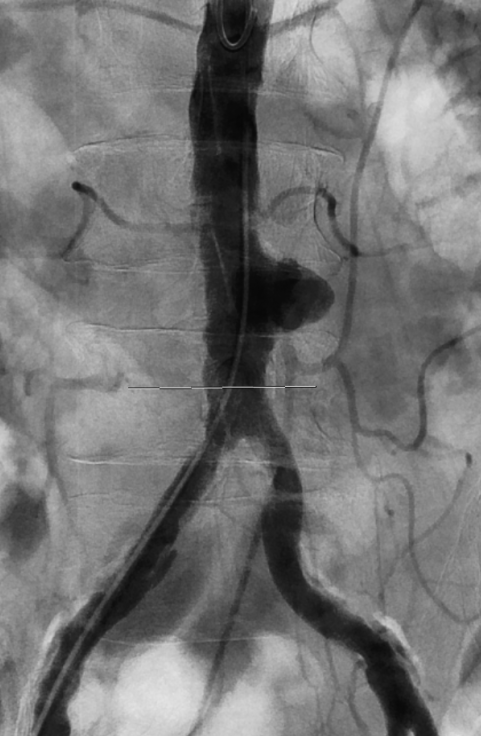

This was treated by interventional radiology using pinhole techniques. A small access was placed in the right groin artery (right CFA) and repair was done endovascularly using a Medtronic Renu cuff. The device was placed percutaneously and the access site closed using Proglide closure device by Abbott.